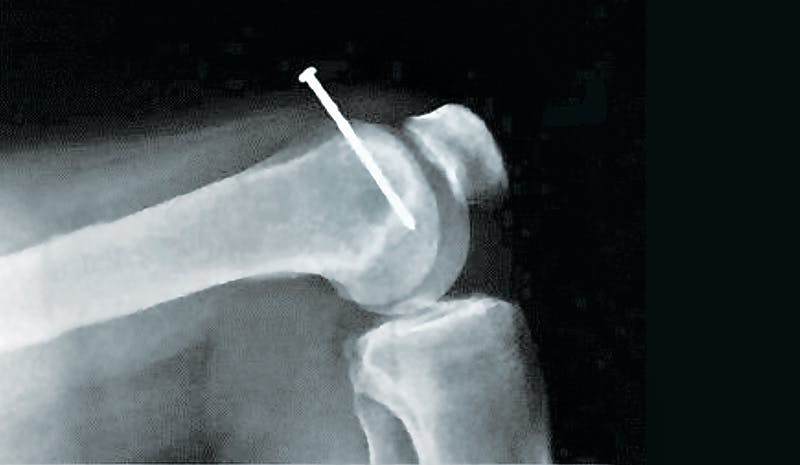

The first time Shawn Mahler nailed through bone happened while shooting sole plates into a subfloor. He ran out of hose, so he gave the nail gun a yank. That pulled his hand down, pushing the gun tip into his boot. The result was a nail through the foot—the picture below is the X-ray Mahler got in the emergency room before they yanked the nail. He lost a month of work.

One finger came unstuck when he shook his hand, but the nail went clean through the other (photo opposite) and required a visit to the hospital to remove it.